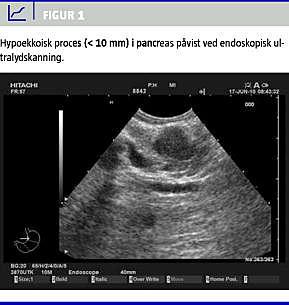

Patienten blev henvist til en kirurgisk afdeling med henblik på endoskopisk ultralydskanning (EUS). Denne undersøgelse viste to forandringer på overgangen mellem corpus og cauda pancreatis. I den ene, en 8 mm, let spikuleret og hypoekkoisk forandring, blev der forsøgt finnålsaspiration med henblik på diagnose. I forbindelse med dette fremkom et hæmatom, hvori processen forsvandt. 1,5 cm perifert herfor sås en 6 mm stor, mere hypoekkoisk og fuldstændig velafgrænset proces. På grund af patientens komorbiditet fandtes han ikke egnet til hverken åben eller laparoskopisk kirurgi. Man valgte i stedet at forsøge behandling med alkoholsklerosering, og idet der fremkom et hæmatom i den største af de to processer, valgte man udelukkende at injicere alkohol i den mindste. Der blev i alt injiceret 3,5 ml absolut alkohol (98%) i den mindste tumor (Figur 1 ).